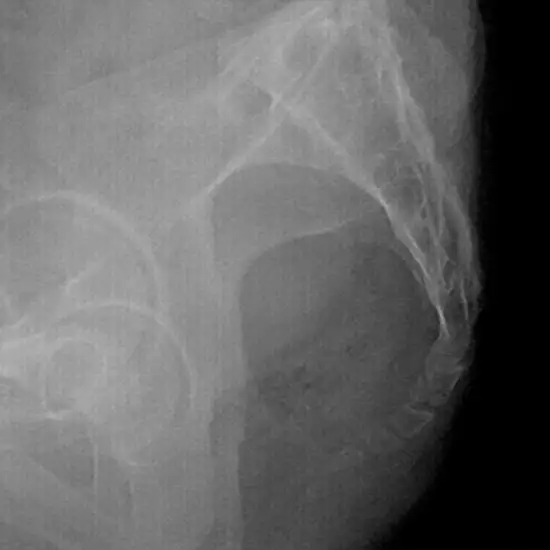

Coccyx LAT X-Ray View displays the most distant portion of the spine in a lateral position. It is used to demonstrate the sacrum and coccyx anatomy and determine the reason for coccyx pain. The coccyx, also commonly known as the tailbone, is a tiny, triangular bone found at the base of the spine that resembles a shortened tail.

The doctor suggests this test if the coccyx has been fractured due to a sudden fall onto the buttocks. In extreme circumstances, the coccyx may require surgical removal.